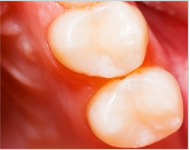

除净病变组织,保护牙髓和健康牙齿组织,建立良好的固位形和抗形,以免造成继发龋。

材料填充,即时雕刻外形,除去超过咬合面过高的部分,以防刺激牙龈引起炎症。